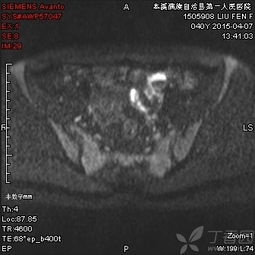

6、盆腔內(nèi)病變:包括膀胱、前列腺、子宮、卵巢、直腸良、惡性占位病變,特別是前列腺增生,子宮內(nèi)膜異位癥等。MRI多方位、大視野成像可清晰地顯示盆腔的解剖結(jié)構(gòu)。尤其對(duì)女性盆腔疾病具有重要診斷價(jià)值,對(duì)盆腔內(nèi)血管及淋巴結(jié)的鑒別較容易,是盆腔腫瘤、炎癥、子宮內(nèi)膜異位癥、轉(zhuǎn)移癌等病變的最佳影像學(xué)檢查手段。